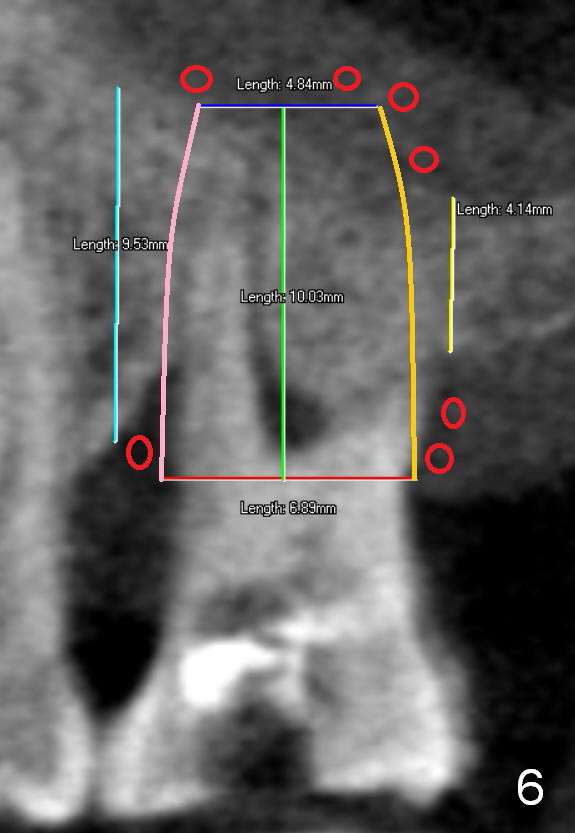

Two years post RCT, there is radiolucency around the MB root of the tooth #3 (Fig.1,2). Eleven days later, there is acute infection associated with MB and DB root fracture (Fig.3). According to the X-ray taken 11 days earlier (Fig.1,4), a long tissue-level implant (6x17 mm) is suitable for the site. In accordance with CBCT (coronal (Fig.5) and sagittal (Fig.6) sections) taken prior to RCT, a short bone-level implant (6.9x10 mm) is a more reasonable choice.